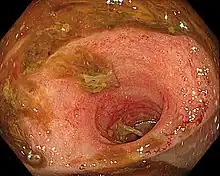

Ileítis es la inflamación del íleon, una parte del intestino delgado. La ileítis de Crohn es un tipo de enfermedad de Crohn que afecta el íleon. La ileítis es causada por la bacteria Lawsonia intracellularis.[1] La enfermedad de inflamación humana del intestino no se encuentra asociada con la infección por Lawsonia intracellularis.

Ileitis caused by capecitabine